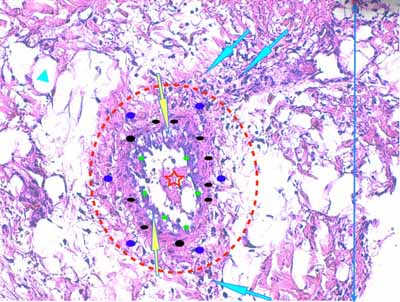

Photo 9 (Hémalun-Eosine X200) : une artériole hypodermique de moyen calibre

montre une vacuolisation de ses cellules endothéliales et un épaississement

de sa media et de son adventive. Sa lumière abrite un fragment de

thrombus fibrineux. L’hypoderme environnant est œdémateux.

Légendes de la Photo 9 :

- Flèches jaunes : vésiculation de l’espace sous-endothélilae et des cellules endothéliales

- Flèches turquoises : œdème et infiltrat neutrophilique dilacérant les adipocytes des lobules adipeux de l’hypoderme

- Pointe de flèche turquoise : adipocyte

- Ovale rouge pointillé : artériole de moyen calibre

- Ronds verts : endothélium de l’artériole

- Ronds noirs : media de l’artériole

- Ronds bleus : adventice de l’artériole

- Double flèche bleue : hypoderme

- Étoile rouge : thrombus fibrineux ostruant la lumière de l’artériole